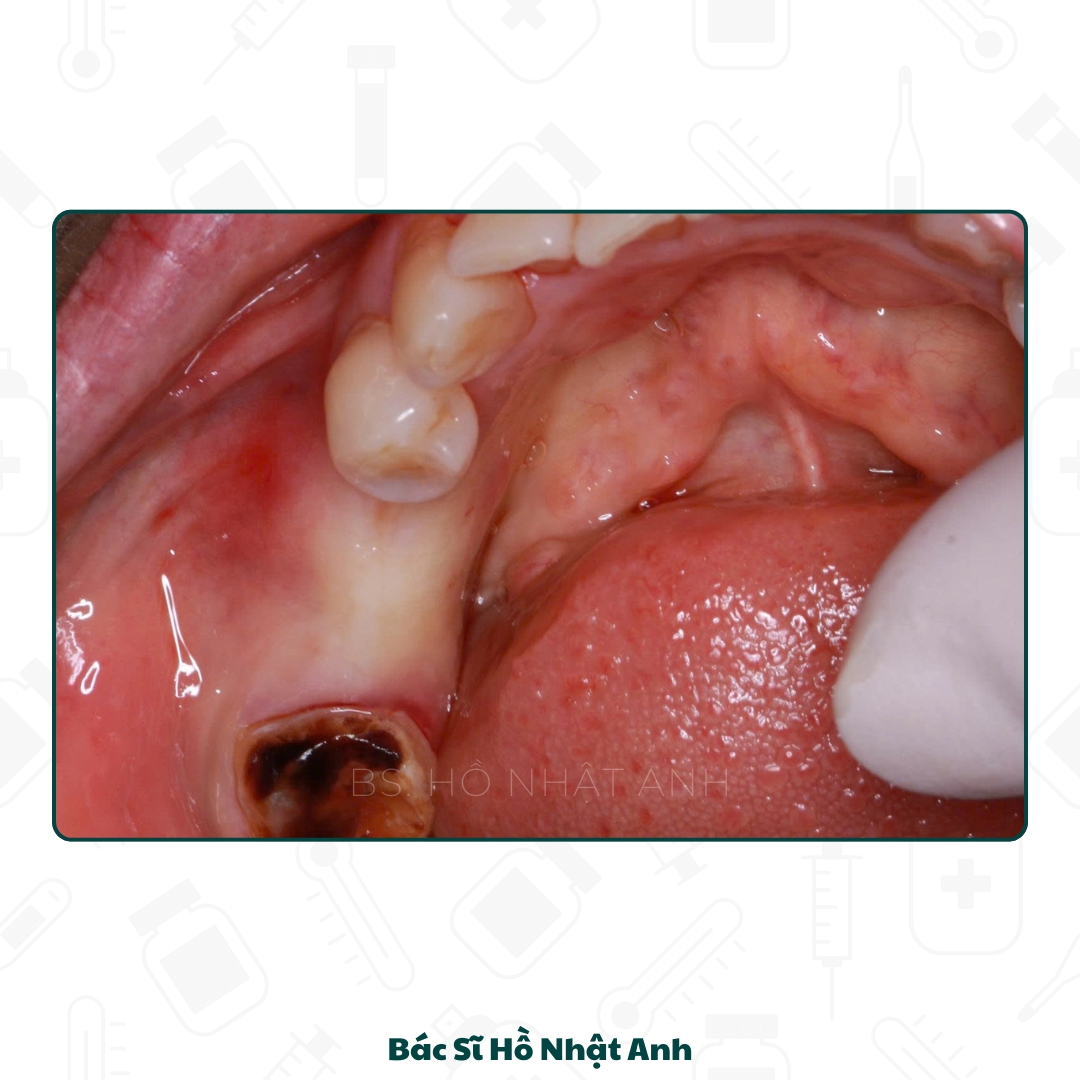

Quy trình cắm Implant, Ghép xương, xử lý mô mềm Và Lắp răng

Quy Trình Cắm Ghép Implant